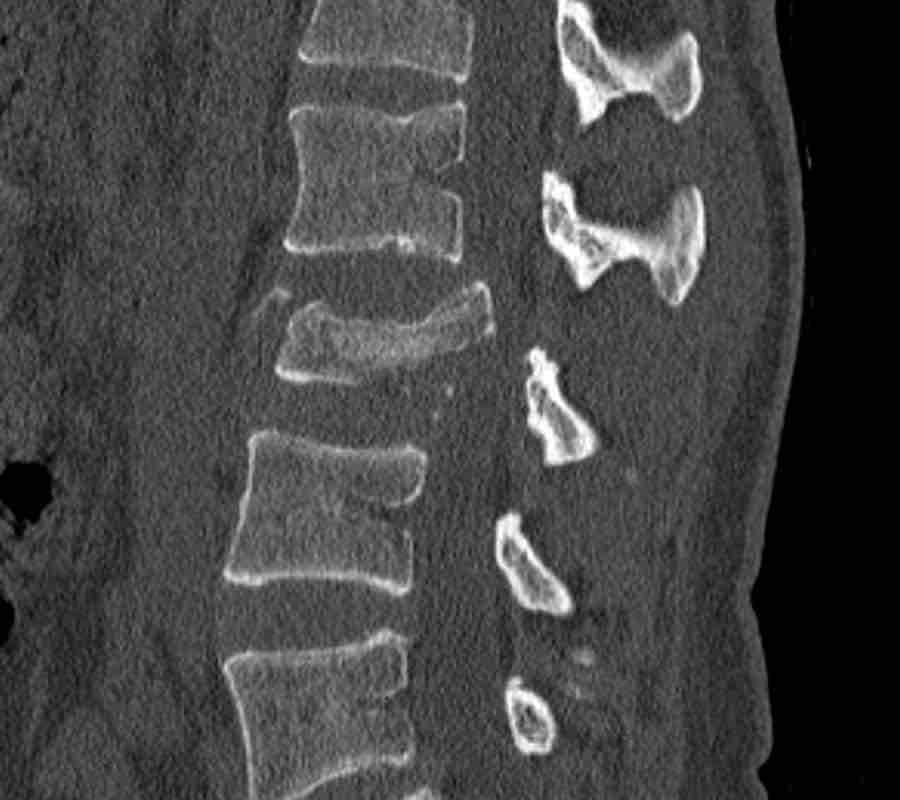

These images are of a 65 year-old woman who fell from her bike.

Scroll through the images.

What are the findings?

What is the highest AO-type of injury?

Findings

There is a type C injury.

In addition to the dislocation in the upper thoracic spine, there is also a sternum fracture, further increasing instability alongside the severe spinal injury.